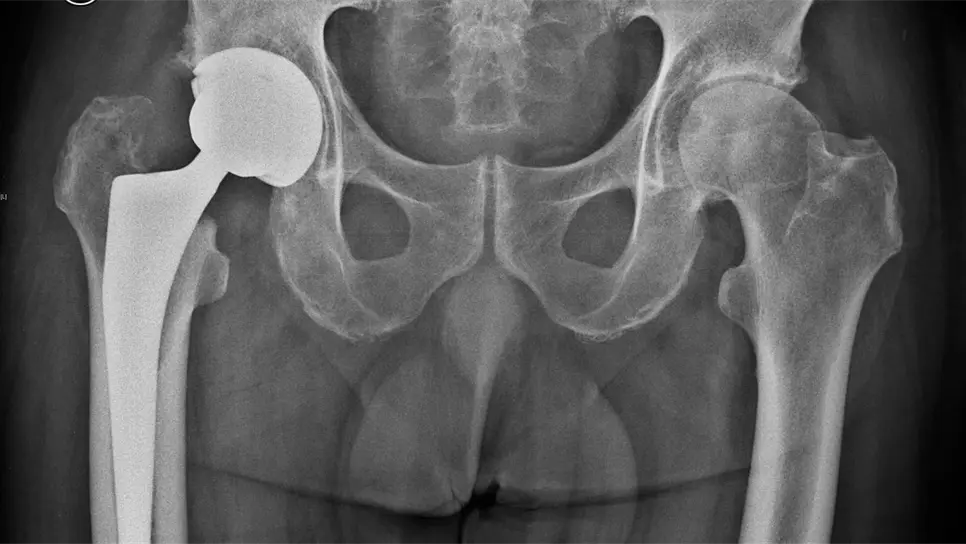

Cirugía inmediata tras fractura de cadera disminuye riesgo de muerte

Ciudad de México.- La fractura de cadera tiene una alta incidencia en personas mayores de 65 años de edad y constituye una de las principales causas de muerte en ese sector de la población.

Se calcula que la mitad de los pacientes muere en los seis meses posteriores a la lesión y gran parte de los sobrevivientes no recupera su nivel previo de independencia y funcionalidad, además de presentar afectaciones en cuanto a su equilibrio físico, mental, funcional y social.

Subrayan que la pronta solución quirúrgica disminuye la mortalidad por fractura de cadera y puntualizan que lo ideal es realizar la cirugía el día de ingreso al hospital o a más tardar un día después, siendo el principal obstáculo para ello la falta de disponibilidad de quirófanos o cirujanos.

También indican que entre más demore la cirugía el riesgo de complicaciones es mayor, siendo las principales: infecciones del tracto urinario, neumonías, tromboembolismo pulmonar, úlceras por presión y otros problemas cardiovasculares.

Los expertos detallan que 95 por ciento de los casos de fractura de cadera en pacientes mayores de 65 años son causados por una caída desde su altura.